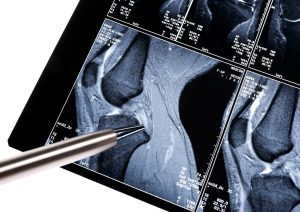

En primer lugar, a todos se les realizó una resonancia magnética de referencia de las rodillas y caminaron en una cinta para registrar la mecánica de su marcha.